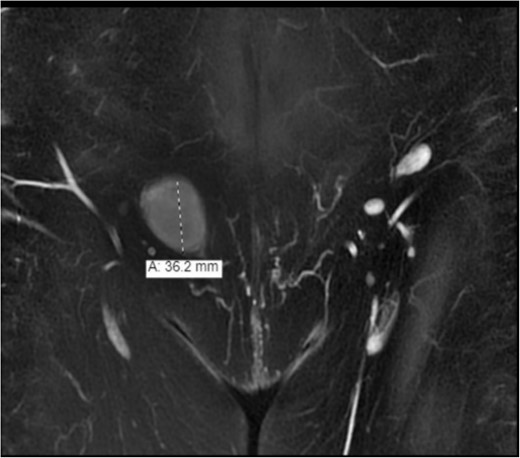

Further assessment by enhanced computed tomography (CT) of the abdomen and pelvis showed a heterogeneously enhanced, well-defined lesion in the right inguinal canal with no surrounding fat stranding or lymphadenopathy. The result corresponded to a hypoechoic lesion seen on the ultrasound with a lamellated appearance, suggesting a nerve sheath tumor or other tumors related to the round ligament, such as leiomyoma/fibroma (Fig. 2). The magnetic resonance imaging (MRI) showed an enhancement and solid lesion in the right inguinal area (Fig. 3).

The MRI showed an enhancement and solid lesion in the right inguinal area.